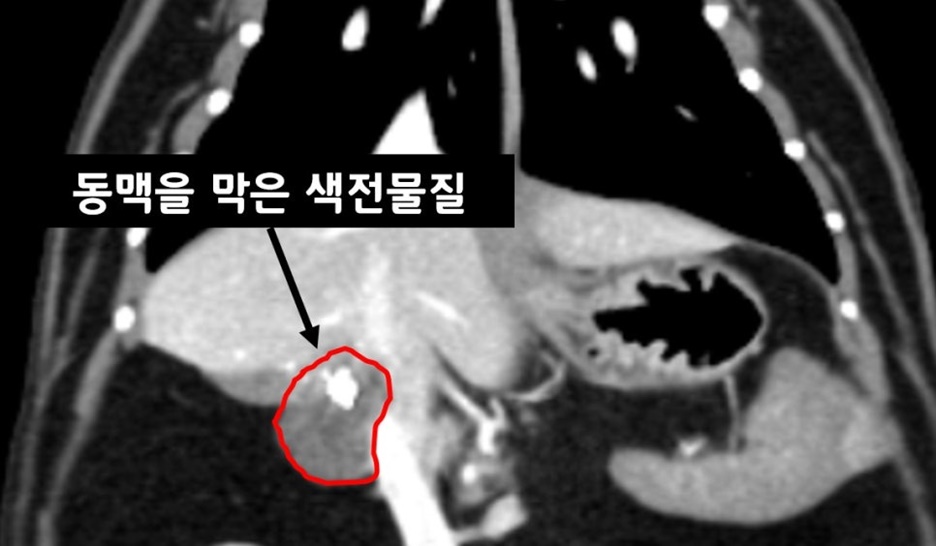

▲ 색전술 시술 10주 차

10주 차 CT 촬영에서는 종양의 대략 50%의 크기 감소를 확인했고 종양의 영양 동맥(Feeding artery)을 막은 색전 물질이 확인됩니다. 활력과 식욕 모두 양호했으며 주변 장기로의 침습과 전이도 진행되지 않았습니다.